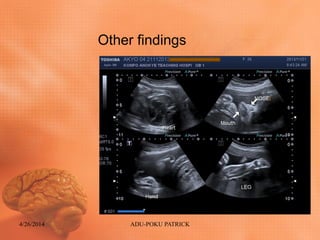

OTHER FINDINGS

• Heart occupying about 3/4 of chest cavity

(CARDIOMEGALY) how ever no visible

defect and effusion noted.

• Normal Sonographic appearance of :

 Nose and lips

 Limbs and digits

 Spine was also intact

 Adequate AFI (16.4cm)